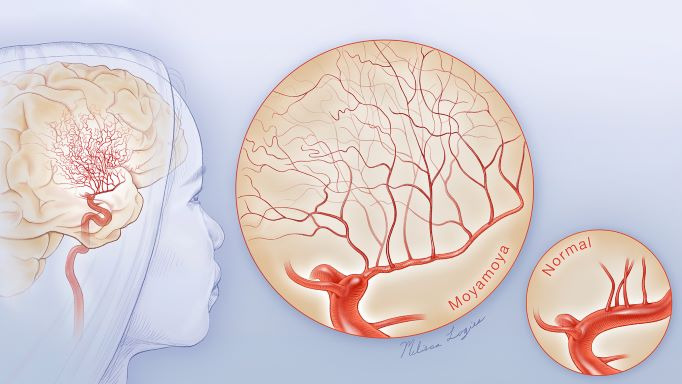

모야모야병은 뇌 기저부에 있는 주요 혈관이 점차 좁아지면서 뇌로 가는 혈류량이 줄어드는 질환입니다. 혈류가 부족해지면 뇌는 새로 가늘고 약한 혈관을 만들어 혈류를 보완하려고 하는데, 이 혈관들이 모여 있는 모습이 연기처럼 보여 ‘모야모야’라는 이름이 붙었습니다.